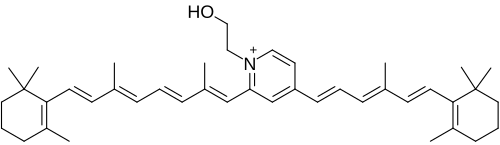

The ABCR -/- knockout mouse has delayed dark adaptation but normal final rod threshold relative to controls.[13] Bleaching the retina with strong light leads to formation of toxic cationic bis-pyridinium salt, N-retinylidene-N-retinyl-ethanolamine (A2E), which causes dry and wet age-related macular degeneration.[14] From this experiment, it was concluded that ABCR has a significant role in preventing formation of A2E in extracellular photoreceptor surfaces during bleach recovery.